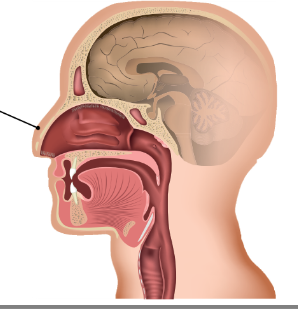

Parts of the Upper Respiratory Tract

Nose, Nasal cavity, Sinuses, Pharynx, and Larynx (voice box)

Nasal cavity

primary passageway for air in and out of the respiratory system

Nasal septum

cartilage that divides the nasal cavity into two

SInuses

four pairs of hollow spaces in the skull that open into the nasal cavity

Pharynx

located behind the nasal cavity and mouth; connects nose, mouth, and larynx; functions as a passageway for air moving from the nasal cavity to the larynx and food moving from the mouth to the esophagus

Name the 3 Parts of the Pharynx

Nasopharynx, Oropharynx, and Laryngopharynx